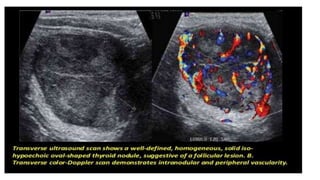

Thyroid adenoma